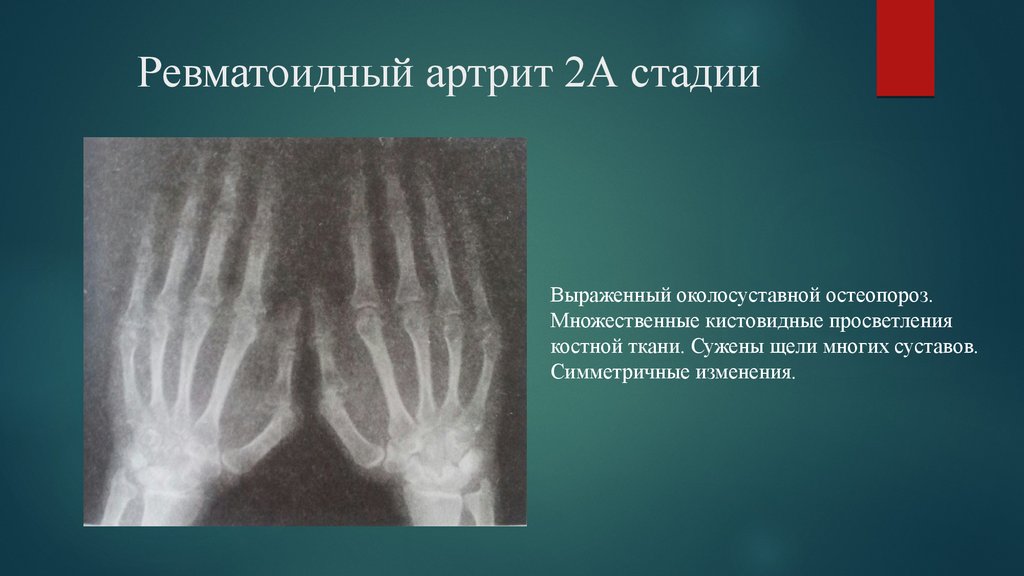

Ревматоидный артрит стопы: рентгеновские снимки и стадии заболевания

Раздел: Визуальный дайджест